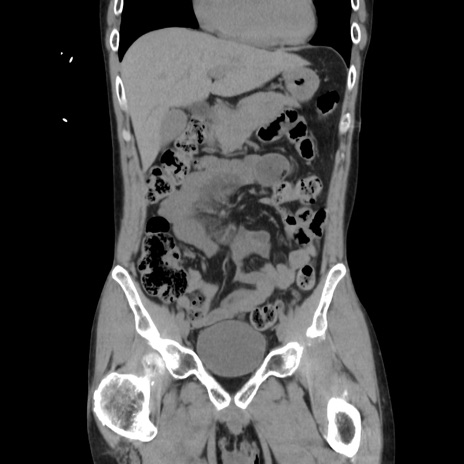

症例37(冠状断像)

【症例】40歳代 男性

【主訴】腹痛

【現病歴】4時間ほど前に電車に乗車中に臍部上より腹痛出現。徐々に増悪し起立困難となり、救急外来受診。生ものは数日食べていない。今朝お雑煮を食べた。

【身体所見】BT 36.8℃、BP 117/84mmHg、HR 91/min、SpO2 97%、苦悶様、腹部:臍上部広範囲圧痛あり、反跳痛±

【データ】WBC 8100、CRP 0.03